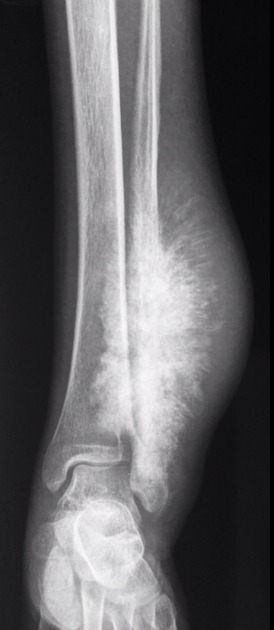

Signs And Symptoms of bone cancer-Dr.Anwar Amir ansari ...

Signs And Symptoms of bone cancer-Dr.Anwar Amir ansari ... from i.ytimg.com

Approximately 800 new cases of. Osteosarcoma is an aggressive and malignant bone tumor most commonly appearing around the knee and shoulder in adolescents and young adults. Some inherited bone conditions can raise the risk of osteosarcoma. Effects of glucosamine, chondroitin, or placebo in patients with osteoarthritis of hip or knee: Usually located around the knee in diaphysis or meta/diaphysis and does not occur in hands, feet, spine and flat bones. Osteosarcoma is the most common bone cancer in children. Osteosarcoma is the most common type of bone cancer, and accounts for about 3% of boys are more likely to have osteosarcoma than girls, and most cases of osteosarcoma involve the knee. An algorithm recommendation for the management of knee osteoarthritis in europe and internationally. Found as incidental finding or presents with a fracture. Adjuvant multiple drug chemotherapy for osteosarcoma of.

Osteosarcoma Knee - Periosteal Reaction. Imaging characteristics of primary osteosarcoma: Imaging characteristics of primary osteosarcoma: Osteosarcoma is a bone tumor and can occur in any bone, usually in the extremities of long bones near metaphyseal growth plates. Specifically, it is an aggressive malignant neoplasm that arises from primitive transformed cells of mesenchymal origin (and thus a sarcoma). Usually located around the knee in diaphysis or meta/diaphysis and does not occur in hands, feet, spine and flat bones. Children treated with radiation for another cancer also. Osteosarcoma is the most common type of bone cancer, and accounts for about 3% of boys are more likely to have osteosarcoma than girls, and most cases of osteosarcoma involve the knee. Osteosarcoma can cause knee pain or pain and swelling in the affected area. Approximately 800 new cases of. Osteosarcoma is the most common malignant bone tumor.